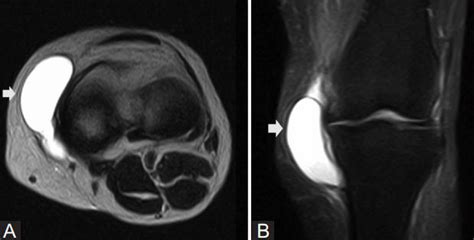

磁共振检查显示:左髋关节积液 盆底左侧软组织肿胀。感觉走路疼痛,求治疗方法。

1、导致髋关节滑膜炎的原因为髋关节滑膜的炎症,细胞渗透性增强,关节腔产生大量积液,导致关节腔内压力升高,使股骨头供血不足,易成为股骨头缺血性坏死的诱发因素,如果治疗方法不当,可转为化脓性关节炎或股骨头缺血性坏死。

2、髋关节积液的因素有很多,包括一般的滑膜炎、髋关节结核等,因此,发现髋关节积液,还需进一步检查确定其具体病因,才能作针对性治疗。目前已经发现左侧髋关节积液伴盆底左侧软组织肿胀,这只是一个现象,并没有查清病因。建议就在现在的这家医院的骨科诊疗。